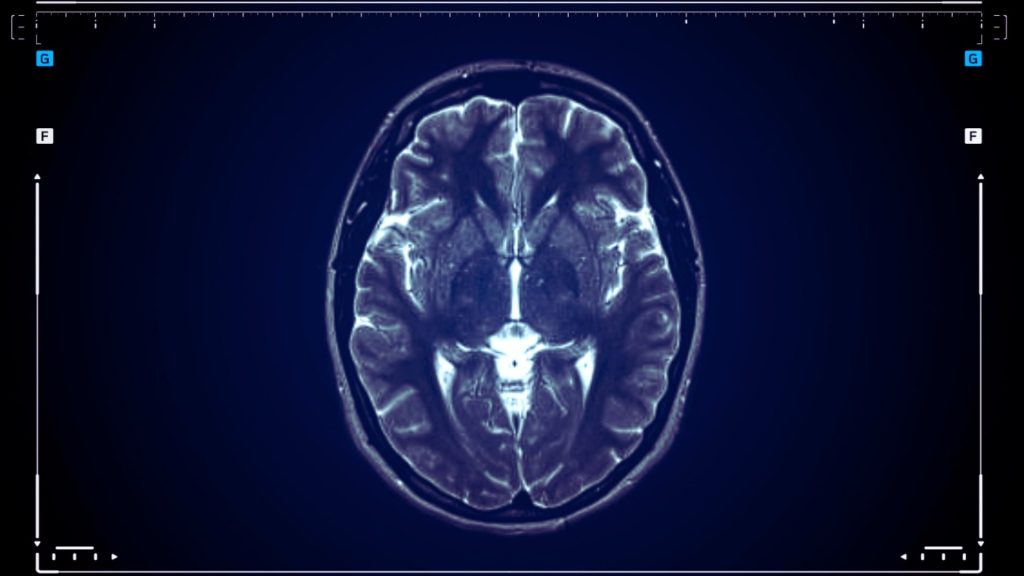

How Fentanyl Affects the Brain and Central Nervous System

Fentanyl targets specific opioid receptors throughout your central nervous system, inundating your system with dopamine while simultaneously dampening pain perception and slowing your breathing rate. Doctors prescribe fentanyl for acute pain following major surgery, chronic pain unresponsive to other pain medicines, and cancer pain that breaks through standard medication.

Your brain contains opioid receptors in areas controlling pain, mood, and basic functions such as breathing. When fentanyl enters your system through a patch, injection, or lozenge in a hospital setting, it attaches to these receptors within minutes and blocks pain signals while triggering reward pathways. The prescription pain medicine mimics your body’s natural endorphins but with dramatically amplified intensity, temporarily rewiring neural pathways involved in pain perception. Because fentanyl can cause life-threatening respiratory depression, clinicians carefully control dosing and monitor breathing, especially during initiation and dose changes.

Repeated fentanyl use restructures your brain’s reward circuits and stress response systems over time, reducing natural endorphin production and changing receptor sensitivity throughout your nervous system. These neurological adaptations create the foundation for physical dependence, where your body requires fentanyl just to feel normal.